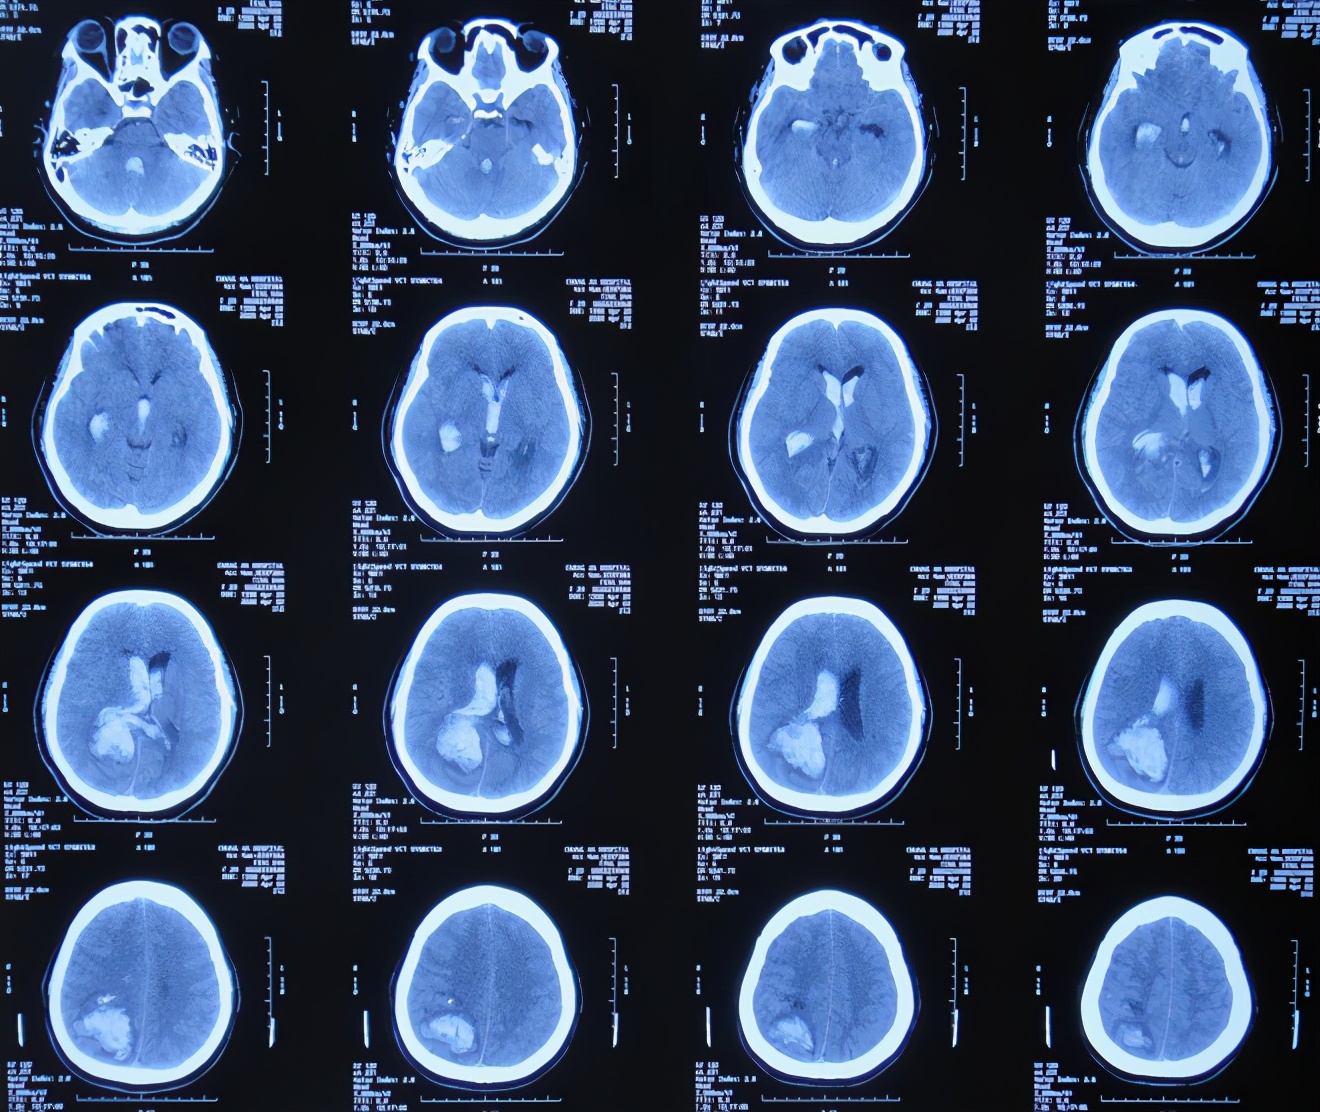

患者于2020年4月2日,在公司上班时突发头痛呕吐,急诊至陕西省西安市某二级医院,急诊查头颅CT检查示右顶叶脑出血破入脑室( 图-1 ),全脑血管造影示脑血管畸形(片子丢失);进行了开颅脑血管畸形切除术+去骨板减压术,术中留置引流外管;术后当天转入ICU继续治疗。

图-1: 2020年4月2日头颅CT